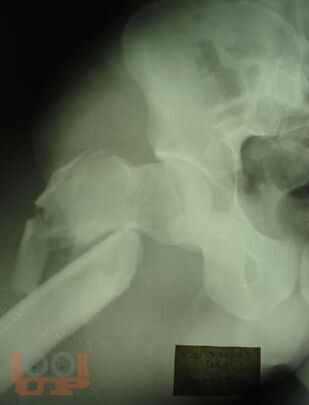

Учебное пособие содержит необходимую информацию для врачей по вопросам оказания специализированной помощи пострадавшим с тяжелой травмой костей нижних конечностей. Подробно освещены вопросы патогенеза шока как основной причины развития травматической болезни, а также тактики оказания специализированной и высоко квалифицированной помощи пострадавшим с тяжелыми монолокальными и множественными переломами костей нижних конечностей в зависимости от периода развития травматической болезни. Особое внимание уделено профилактике и лечению ранних осложнений тяжелых переломов костей нижних конечностей – синдрому жировой эмболии, тромбоэмболическим осложнениям. В пособии обобщен более чем 30- летний опыт лечения пациентов с тяжелой травмой костей нижних конечностей.